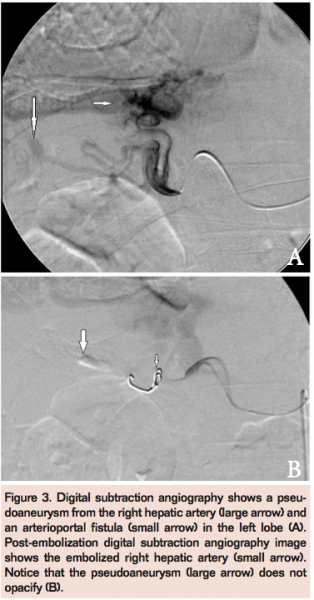

CT angiography (CTA) showed an aortic dissection, which extended from below the level of the superior mesenteric artery to the aortic bifurcation (Figures 1A and 1B). A 16 mm x 18 mm pseudoaneurysm was seen arising from a branch of the right hepatic artery (Figure 1C). There was also an arteriovenous fistula between the left hepatic artery and the left branch of the portal vein (Figures 2A and 2B). A loculated pleural effusion was seen along the posterior aspect of the left chest wall and within the major fissure. Multiple large subpleural bullae were present in both lungs. The coexistence of multiple unusual vascular complications and subpleural bullae in the lungs raised the possibility of a connective tissue disorder. Further physical examination revealed a high arched palate, clubbing, and an increased arm span:height ratio (168:163). There was no hypermobility of joints or hyperextensibility of skin. Serum markers for vasculitis were negative. The possibility of vascular Ehler-Danlos syndrome (VEDS) was considered.

A digital subtraction angiography (DSA) was performed (Figure 3A) and the pseudoaneurysm arising from the right hepatic artery was embolized (Figure 3B) with two 0.18 coils (platinum fibered coils, Boston Scientific/Target Therapeutics) and he was discharged in a stable condition. Three days later, he presented with acute abdominal pain, pallor, and tachycardia. His hemoglobin level was 7.8 gm%. CTA revealed increased dilatation and dissection of the celiac trunk and common hepatic artery (Figure 4) associated with a right-sided perinephric hematoma. He was managed conservatively, given blood transfusions, and discharged on recovery. However, he presented 5 days later with acute abdominal pain, distension, tachycardia, and hypotension. He required intubation and inotropic supports in the intensive care unit. A repeat CT angiography showed aneurysmal dilatation of the celiac trunk and common hepatic artery and extension of the dissection associated with a large pseudoaneurysm (Figure 5). Repeat DSA was done on an emergency basis (Figure 6A) and the aneurysmally dilated common hepatic artery was embolized with 20% Histoacryl glue (Figure 6B). There was no filling of the pseudoaneurysm in the post-embolization angiogram. The patient improved and was discharged when he stabilized a few days later. He died at home a week later.